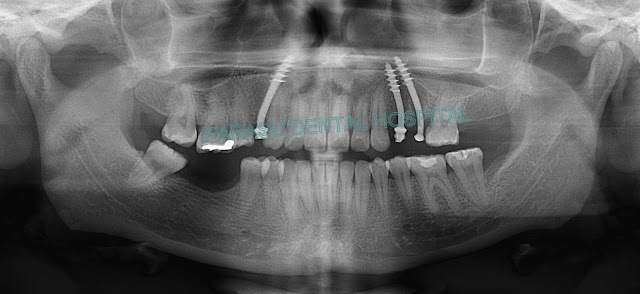

Patient came to our Hospital with Unhappy Smile and deposits in his. Teeth so we Suggest Full Mouth Teeth Cleaning Treatment.. Patient With Happy Smile.